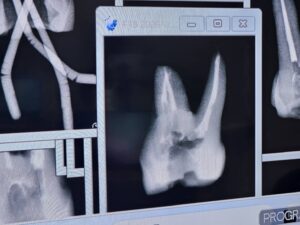

S先生

大阪から来られているS先生のテストケースは以下だ。

彼も上手い。。。

教わる方でなく、教える方だ。

レベチというやつだ。